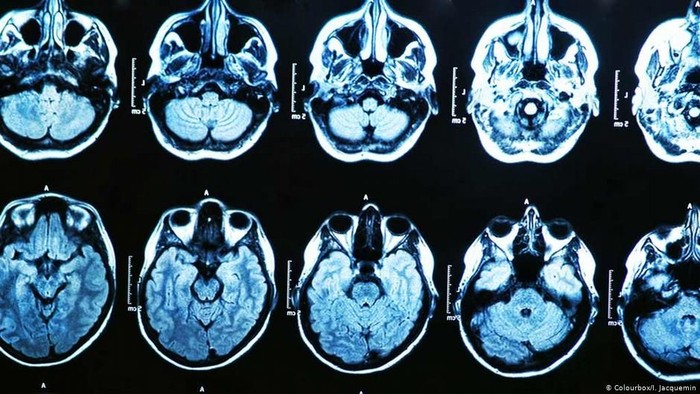

Studi ini melibatkan 26 orang, termasuk kelompok pembanding orang yang belum pernah tinggal di Kuba. Peserta melakukan tes darah dan scan otak. Seekor anjing peliharaan yang mati di Kanada juga ikut diteliti otaknya.